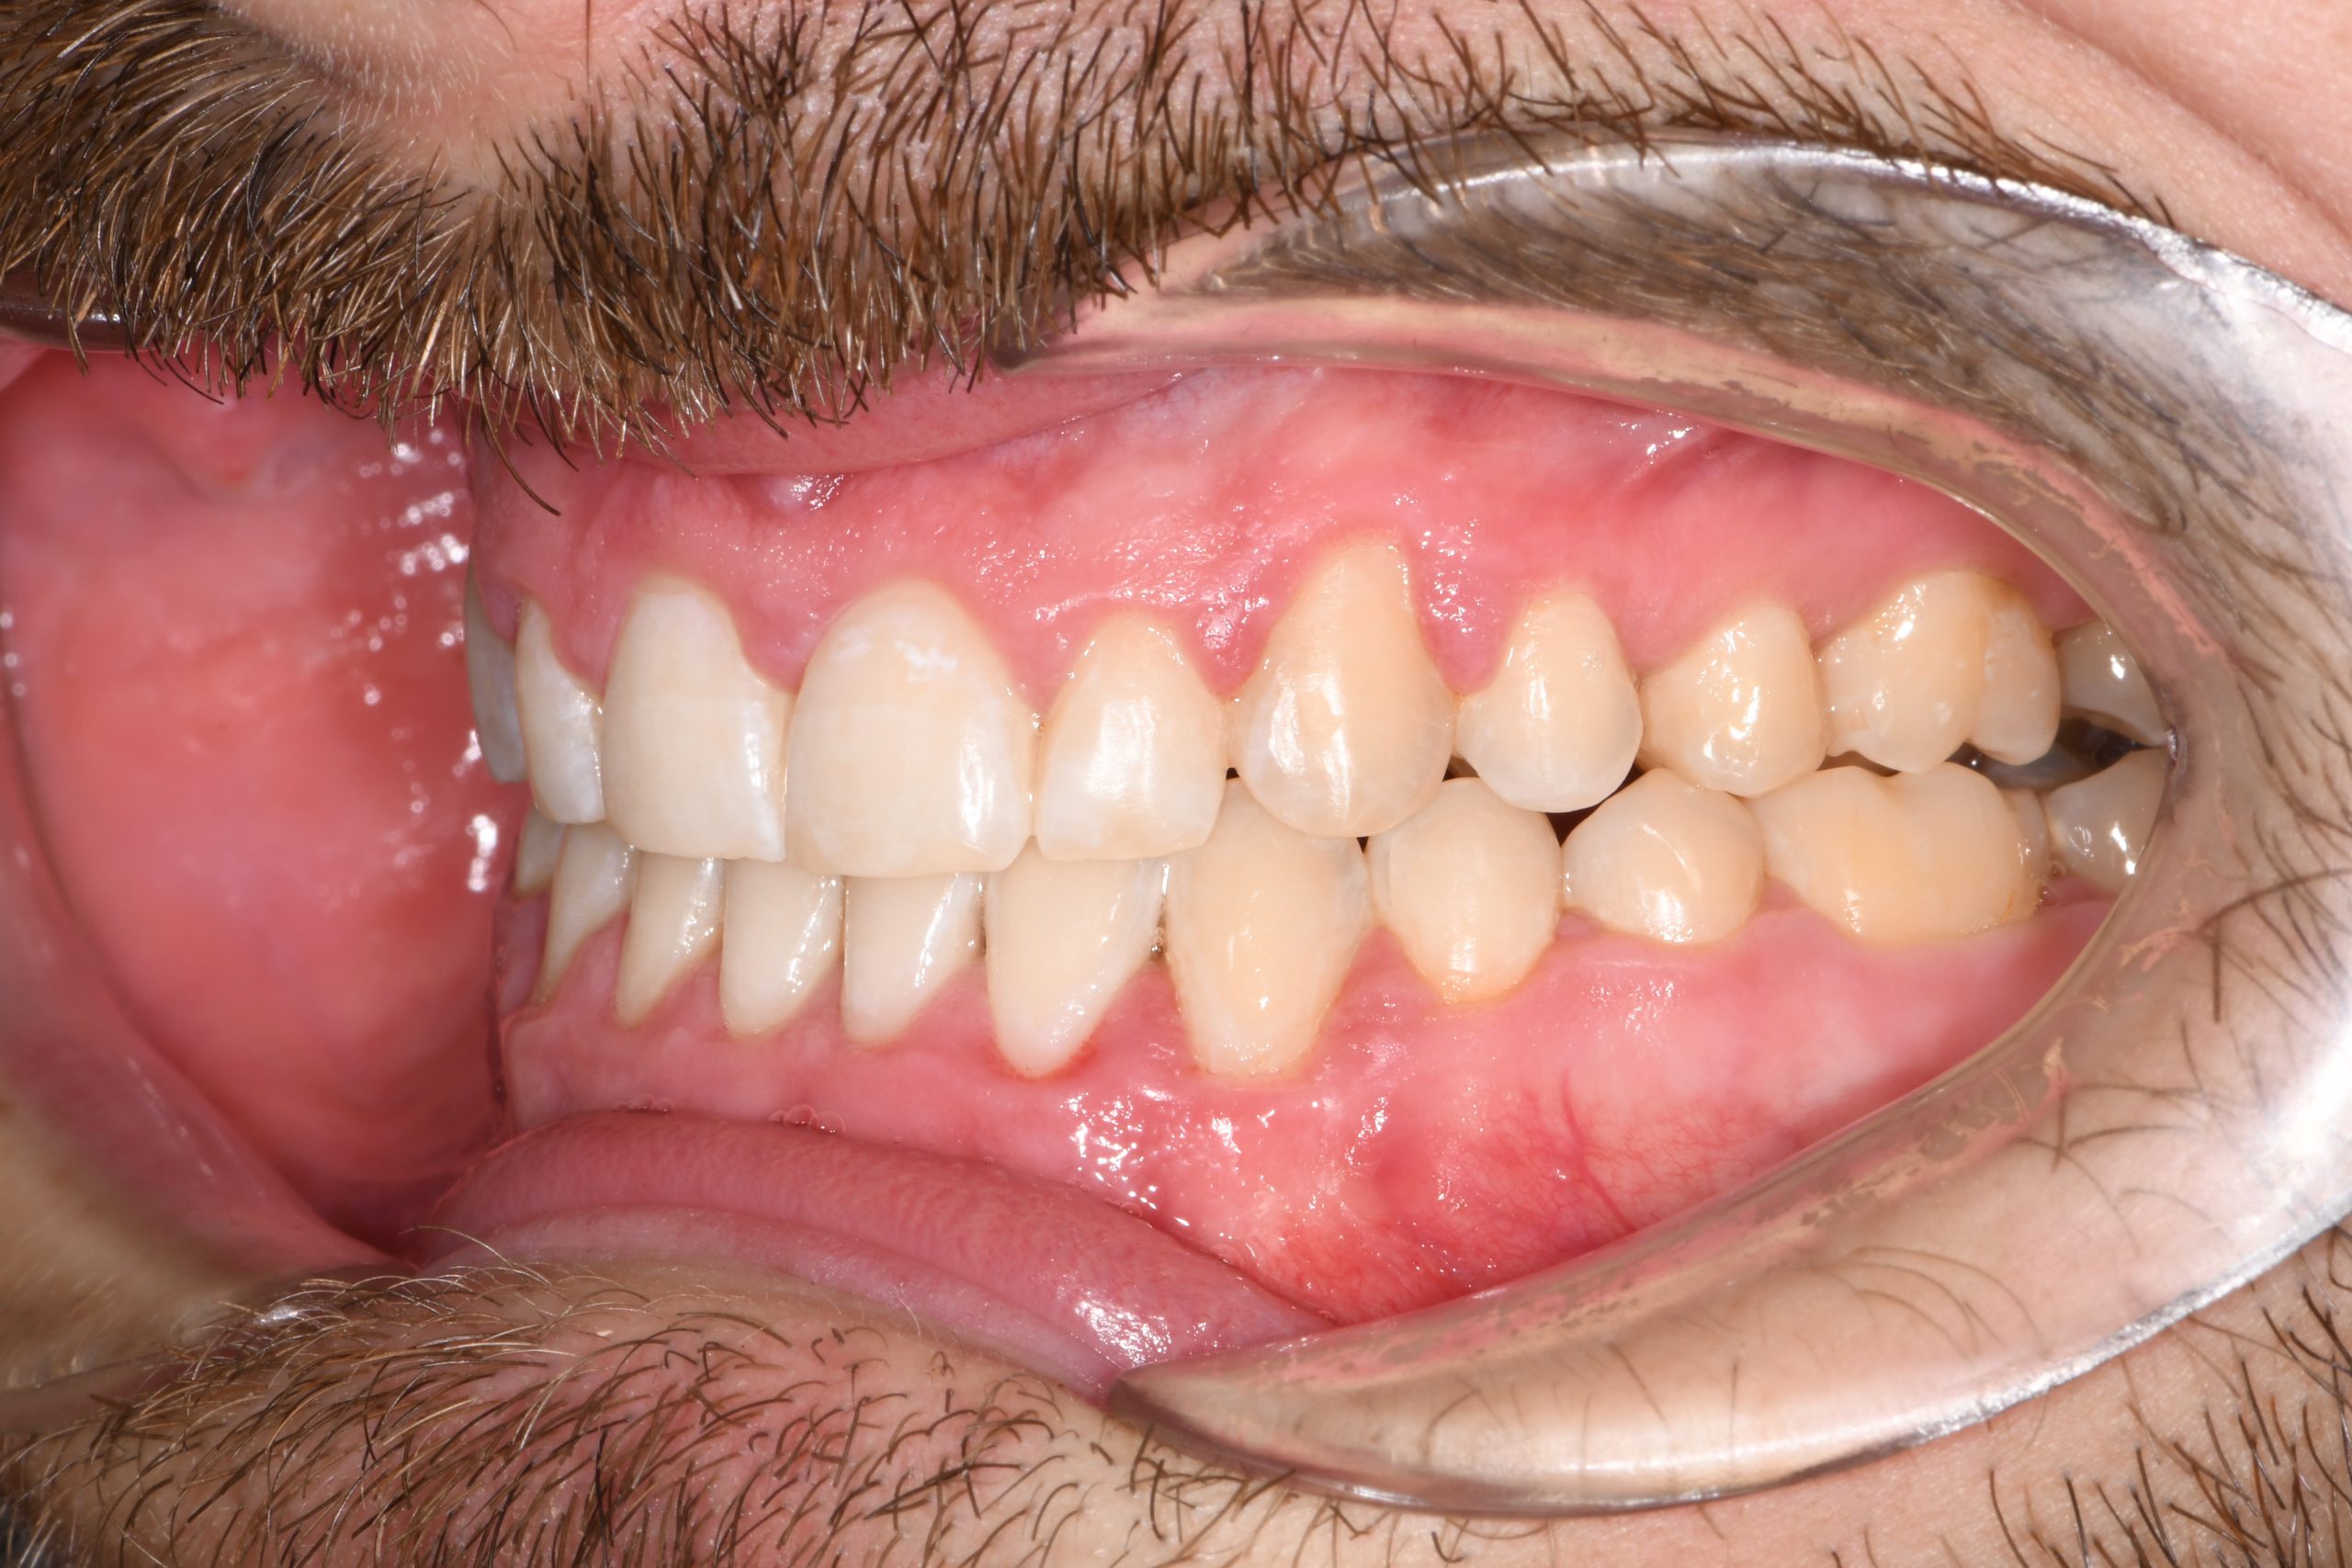

Az elmúlt évekből rengeteg szakmai referenciát tudnánk bemutatni, amelyek különböző fogszabályozási problémákat oldottak meg. Válogatva a több száz esetből, ezen az oldalon olyan képeket, információkat igyekeztünk bemutatni, amelyeknek a segítségével a jövőbeni pácienseinknek azt tudjuk üzenni: A Te fogsorod is lehet gyönyörű!

(Képeket a Pácienseink külön írásos beleegyezésével mutatjuk be!)